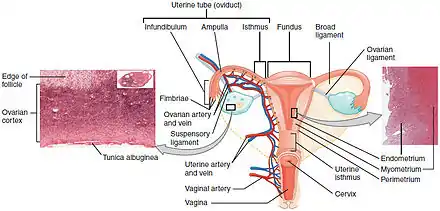

| The location and development of endometrial cancer | |

A diagram showing the female reproductive tract with the uterine wall enlarged and normal endometrium visible | ||||||||||||||||||||||||||||||||||||||||||||||||||||||||||||||||||||||||||||||||

Endometrial cancer forms when there are errors in normal endometrial cell growth. Usually, when cells grow old or get damaged, they die, and new cells take their place. Cancer starts when new cells form unneeded, and old or damaged cells do not die as they should. The buildup of extra cells often forms a mass of tissue called a growth or tumor. These abnormal cancer cells have many genetic abnormalities that cause them to grow excessively.[9]